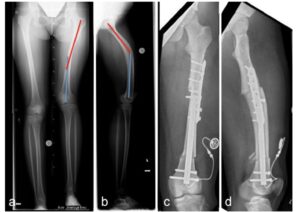

A correção de deformidades ósseas é um dos pilares da ortopedia reconstrutiva moderna e tem como objetivo restabelecer o alinhamento anatômico e funcional dos membros, corrigindo desvios angulares, rotações ou encurtamentos resultantes de condições congênitas, traumáticas ou adquiridas. No CBOT, utilizamos técnicas de osteotomia planejadas digitalmente em 3D, permitindo uma análise precisa da deformidade e uma execução cirúrgica milimétrica. O planejamento tridimensional possibilita prever o resultado final, minimizar erros intraoperatórios e otimizar o posicionamento dos segmentos ósseos.

Entre as principais tecnologias empregadas, destacam-se os fixadores externos hexapodais (como o Taylor Spatial Frame® e sistemas equivalentes), que possibilitam correções multiplanares de forma gradual, segura e controlada. Essas estruturas permitem ajustes pós-operatórios finos, guiados por software, otimizando o resultado funcional e estético.

Sob a coordenação do Dr. Marcelo Pigatto D’Amado, membro da Sociedade Brasileira de Ortopedia e Traumatologia e da AO Foundation, o CBOT é pioneiro no uso de hastes intramedulares motorizadas (PRECICE, FITBONE) para alongamento ósseo no Brasil.